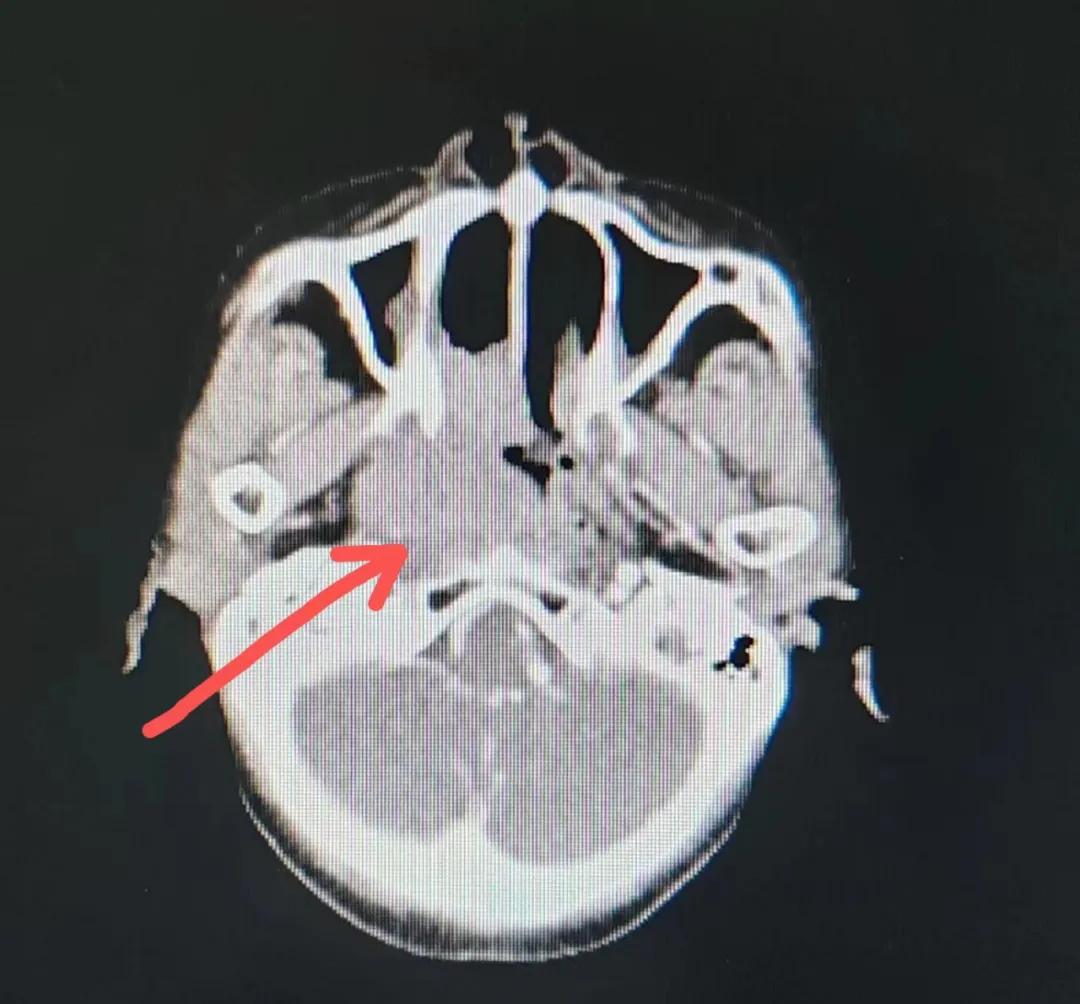

治療后

放療結(jié)束,除了放療處的皮膚輕微放射性皮炎外,基本沒有什么不良反應(yīng)。復(fù)查發(fā)現(xiàn),鼻腔淋巴瘤已不可見,目前患者已康復(fù)出院。